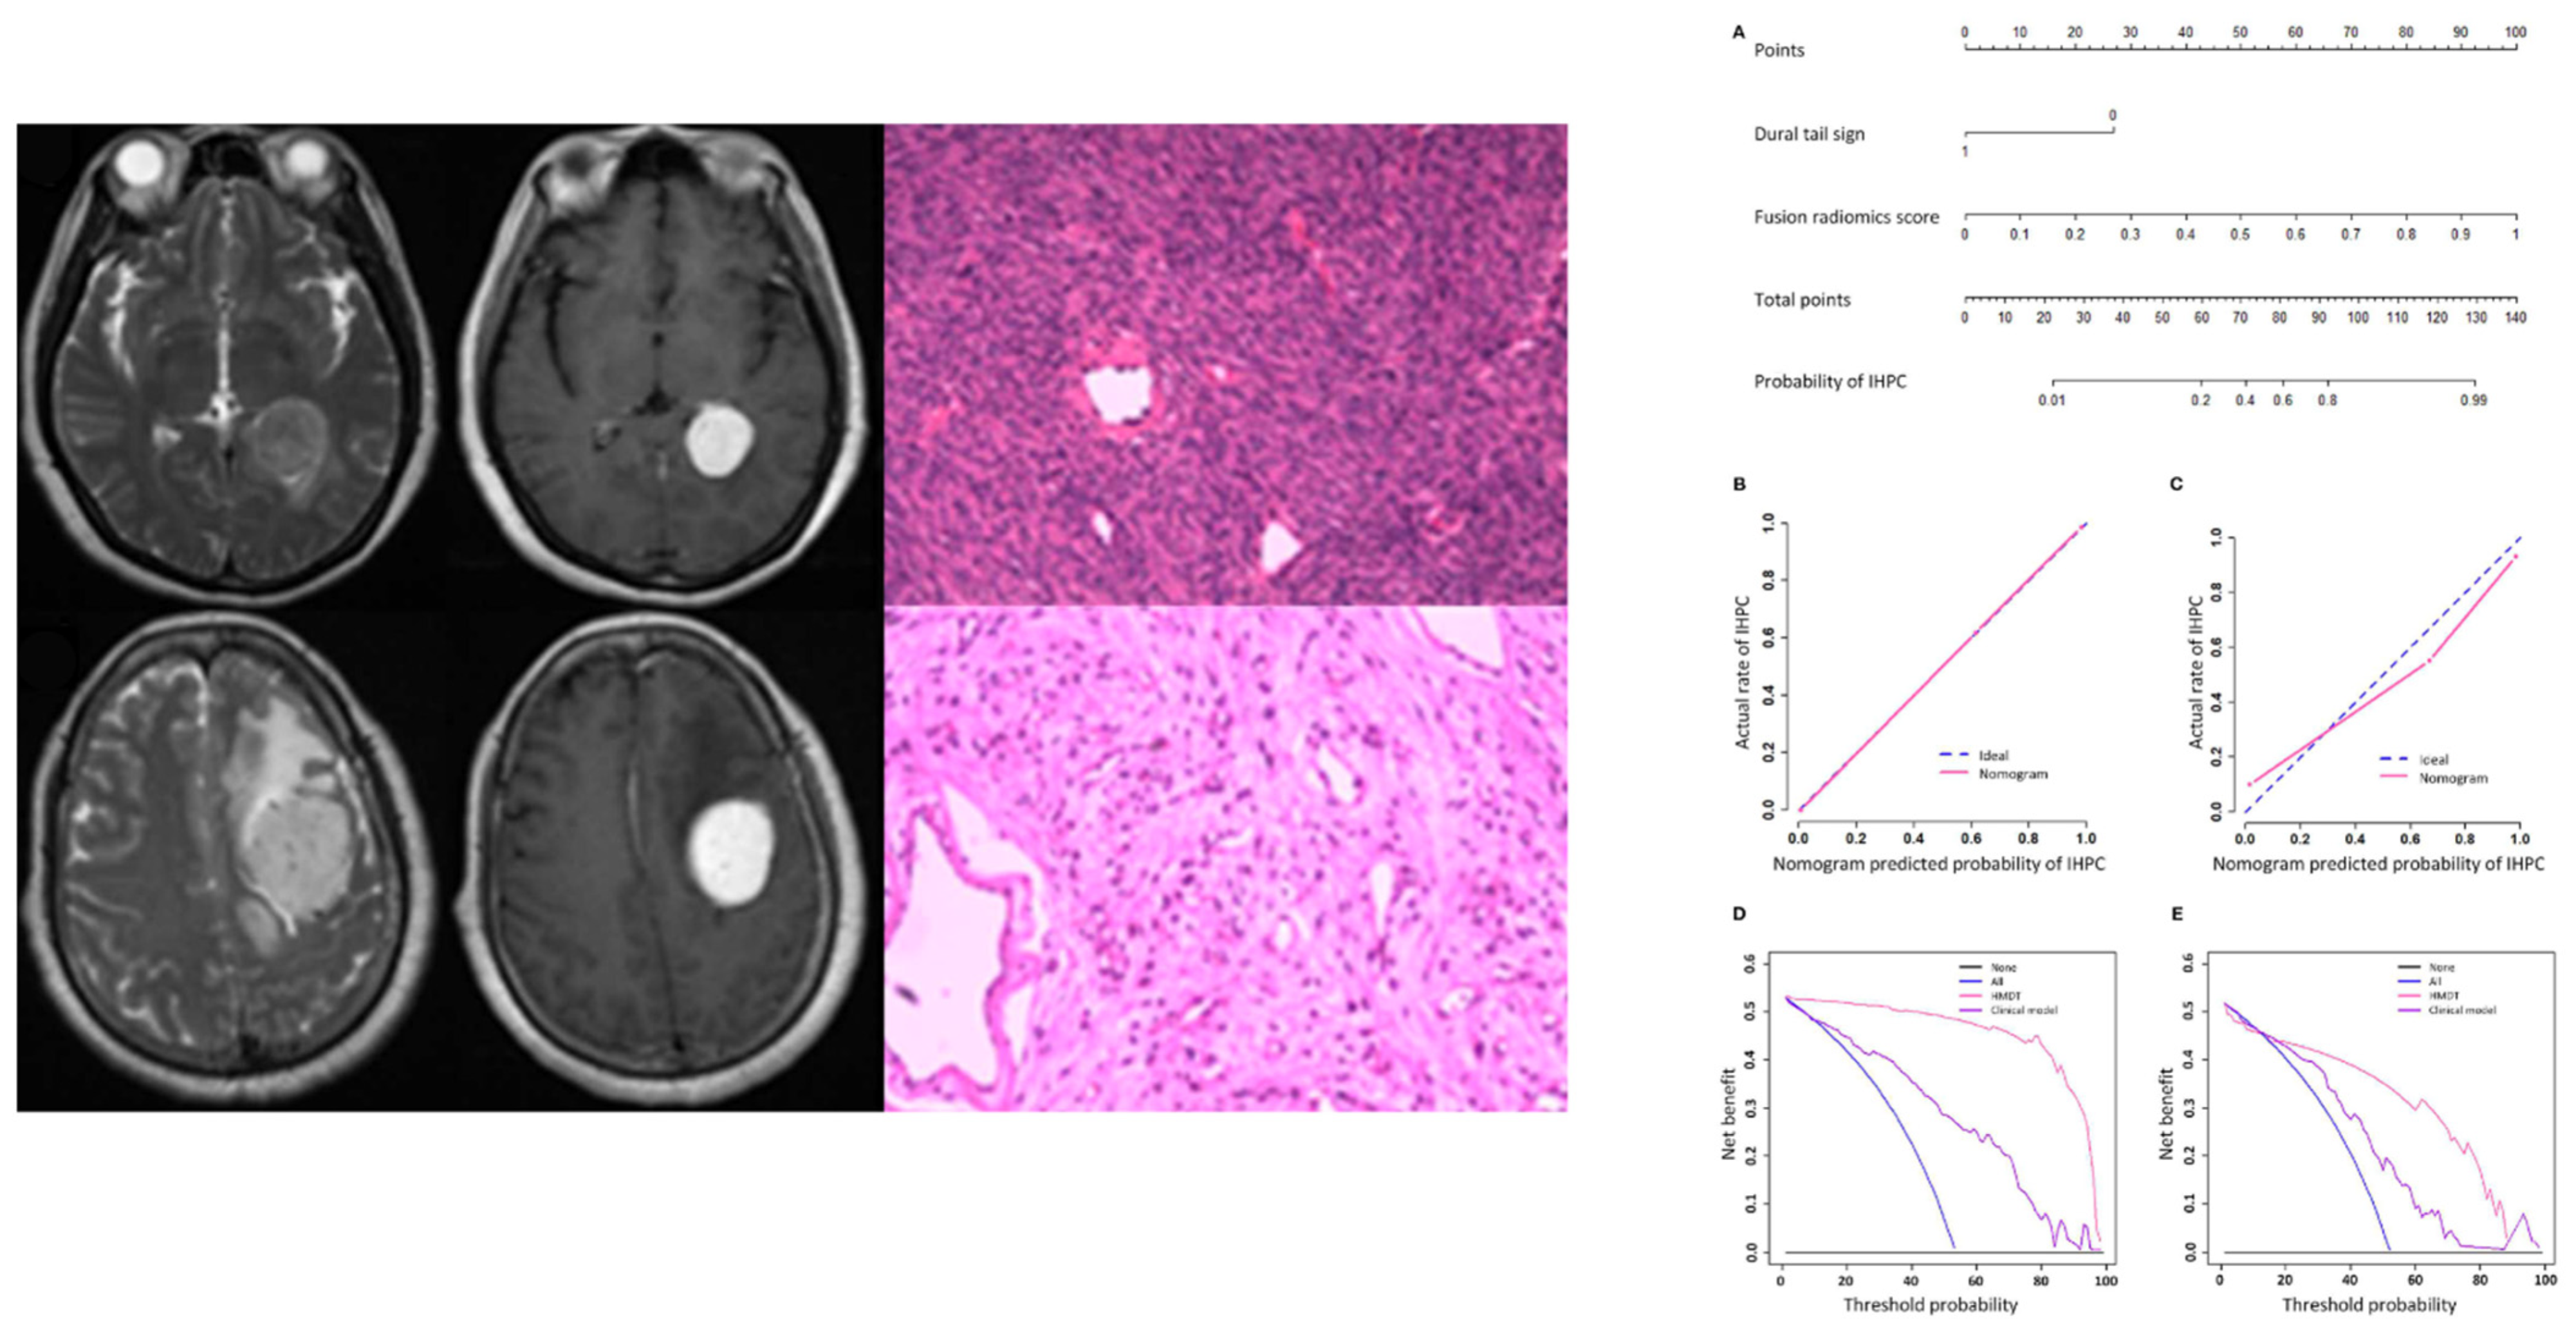

Imaging is generally sufficient to characterize expansive extra-axial lesions such as meningiomas. In some circumstances, however, it may be difficult to distinguish them from other similar neoplasms, in particular solitary fibrous tumor (also known as hemangiopericytoma), very vascularized, potentially causing massive bleeding during surgery, and difficult to differentiate from an angiomatous meningioma on MRI. The differential diagnosis of angiomatous meningioma versus hemangiopericytoma was investigated by Kanazawa et al. [11] They used a texture analysis approach based on contrast enhanced T1- and T2-weighted sequences as well as apparent diffusion coefficient (ADC) maps. The authors showed that ADC entropy and T2 skewness were higher in the case of hemangiopericytoma compared to angiomatous meningioma. Additionally, the mean ADC value was able to differentiate the two lesions with a positive predictive value of 62.5% and specificity of 62.5%. Likewise, Li et al. [14] assessed whether a machine learning model based on texture analysis could allow a differential diagnosis between hemangiopericytoma and angiomatous meningioma. The authors compared clinical and texture features (obtained from FLAIR-, contrast enhanced T1-weighted images and DWI), training four different support vector machine classifiers. They obtained the highest AUC (area under the curve) value (=0.90) when using a contrast enhanced T1-weighted sequence-based classifier. In another study, Wei et al. [20] used a combination of clinical and radiological data to develop an integrated diagnostic tool for preoperative distinction of intracranial hemangiopericytoma from meningioma (Figure 2). This tool demonstrated a remarkable diagnostic accuracy, with an AUC of 0.917 in the validation cohort. Finally, Fan et al. [9] developed a diagnostic model based on a combination of clinical and radiomics features to distinguish the two neoplasms, reporting an AUC of 0.91 in the validation set.

Figure 2.

MR and pathological images of a hemangiopericytoma (upper row) and a meningioma (lower row). Nomogram (A), calibration curves (B,C), and decision analysis curves (D,E) in the training and validation cohorts for differential diagnosis between the two conditions. IHPC: intracranial hemangiopericytoma; HMDT: IHPC and Meningioma Diagnostic Tool. Adapted from Ref. [20], under the terms of the Creative Commons Attribution-NonCommercial 4.0 License.